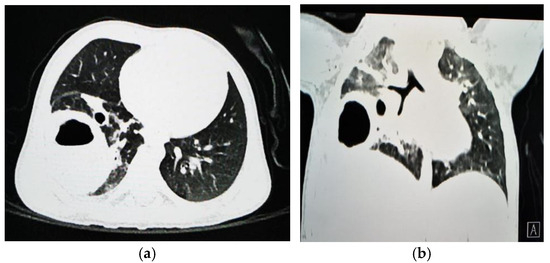

1.9.1. Case 1